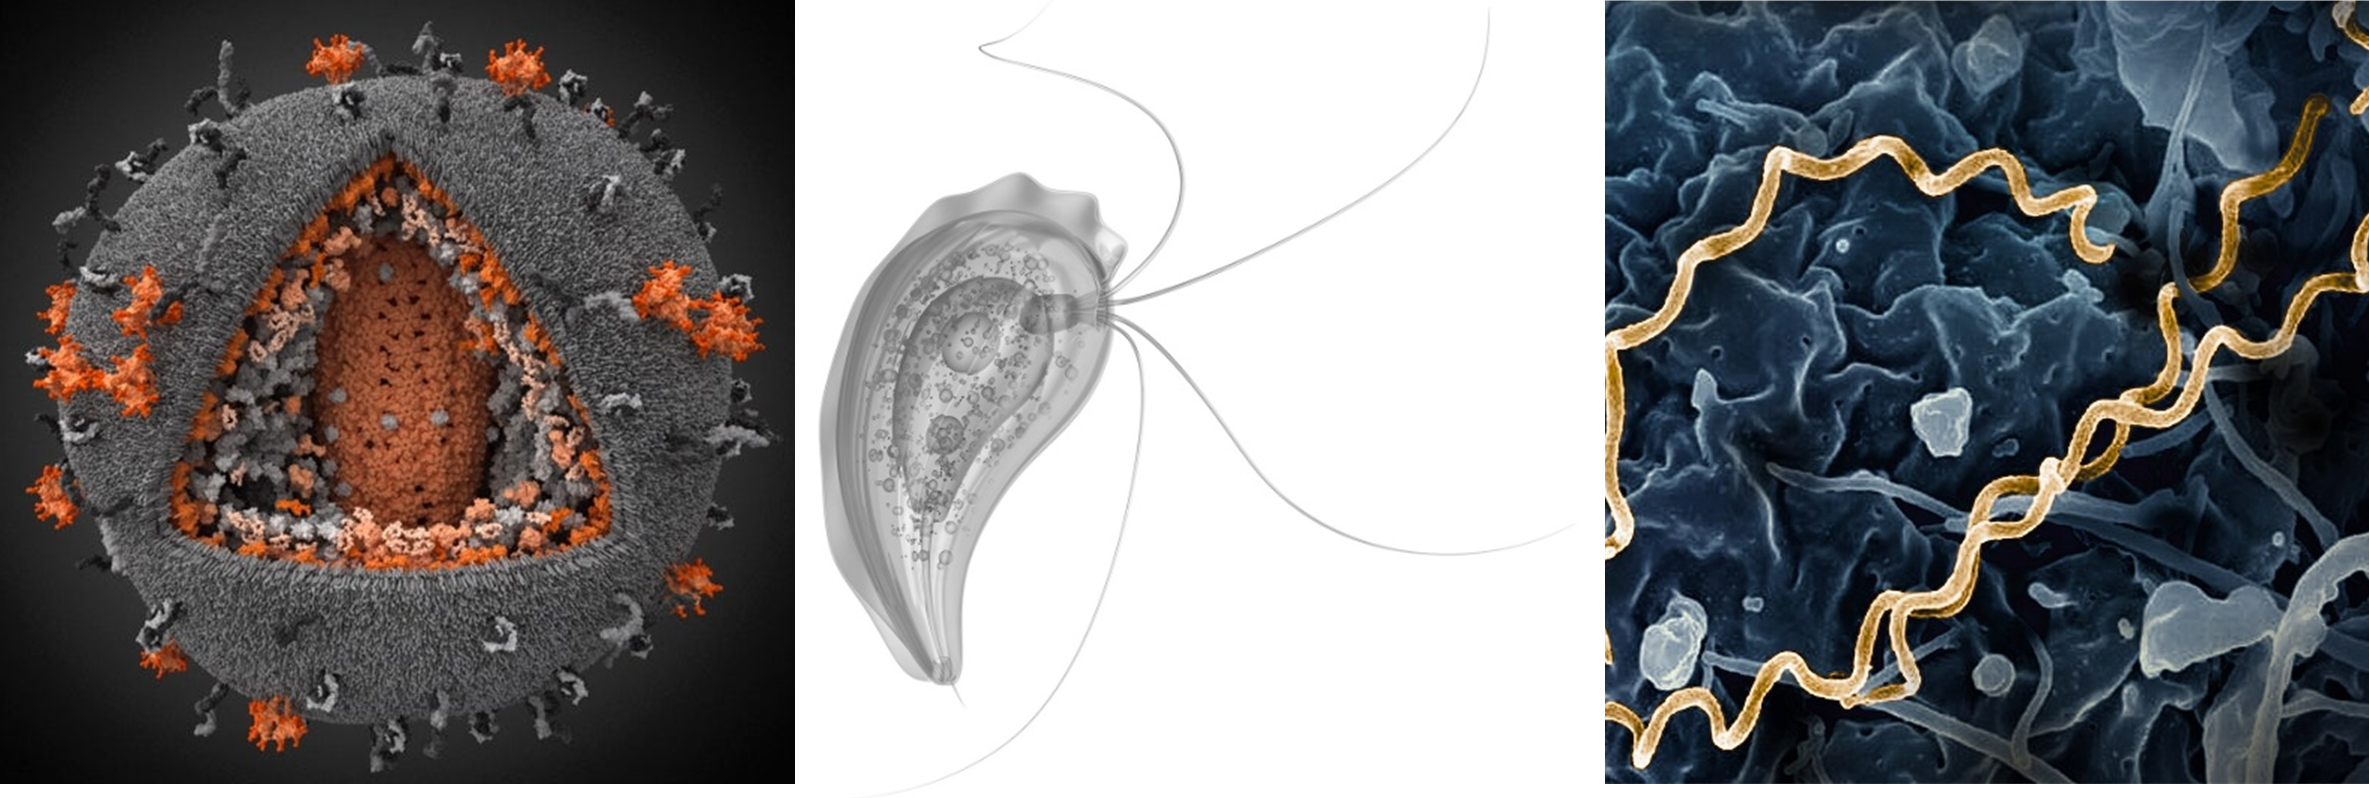

Syphilis

Syphilis is a highly contagious, bacterial infection caused by Treponema pallidum. If left untreated, T. pallidum can cause serious, life-threatening complications. Initial infection presents as firm, round, painless sores, called chancres, that can last 3 to 6 weeks. Untreated syphilis progresses through various stages, from a non-itching rash, followed by a latent (inactive) period for many years, and after 10 to 30 years can progress to a systemic infection damaging organs and possibly resulting in death. During any stage, untreated syphilis can spread to the brain and nervous system causing Neurosyphilis.

HIV and Hepatitis C

DPHL uses a fourth generation Antigen/Antibody Immunoassay test for the early detection of Human Immunodeficiency Virus (HIV) infection. This testing method can detect HIV infection as early as seven days post infection. Confirmation and differentiation of HIV-1 and HIV-2 are available using an immunochromatographic assay.